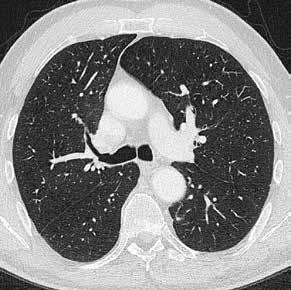

Fall 3:

Thorax-CT im Rahmen einer Lungenkrebsfrüherkennungsstudie. Die Voruntersuchung lag als externe kontrastmittelgestützte Thorax-CT vor. Bei der dosisoptimierten Low-Dose-CT liegt die Strahlenexposition nur noch im Bereich von zwei konventionellen Röntgenaufnahmen des Thorax, die Bildqualität ist für die Fragestellung nach Herdbefunden aber dennoch eindeutig ausreichend, selbst interstitielle Lungenveränderungen lassen sich hier noch beurteilen.

Prof. Dr. med. Johannes Weßling Zentrum für Radiologie, Neuroradiologie und Nuklearmedizin Abb. 3 a: kontrastmittelgestützte Thorax-CT, externe Untersuchung; DLP 216,0 mGy × cm / 3,9 mSv. Abb. 3 b: dosisoptimierte Low-Dose-Thorax-CT, Canon Aquilion Prime SP, Rekonstruktion: AiCE; DLP 13,9 mGy × cm / 0,25 mSv.